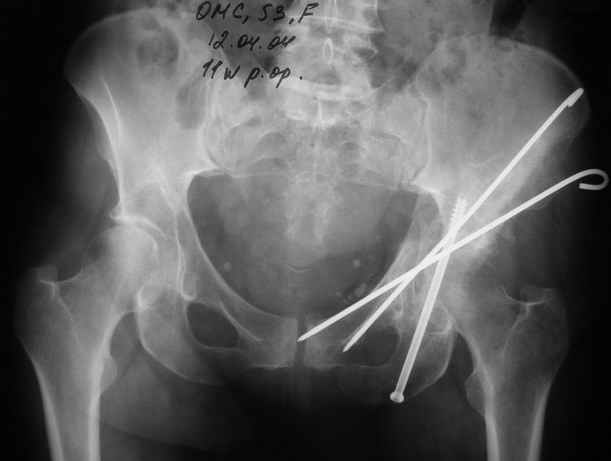

Женя! Класный перелом. Отлично репонируется изнутри таза, но лучше фиксированть сзади. Классический перелом для двустороннего доступа.

Однако есть альтернатива. Репозиция из подвздошного доступа тазовыми щипцами с разнодлинными браншами или тазовым пистолетом, а фиксация задней колонны через седалищный бугор или тазрвыми винтами 4,5 или каннюлированными 6,5 или 7,3. По-моему я посылал на ортофорум такой снимок, когда жаловался на ишемический неврит седалищного нерва через сутки после операции. Не забудь про шейку бедра - мне кажется будет хорош длинный PFN любой фирмы, какую ты найдешь, а нет так UFN + miss a nail, как это здорово делают мои земляки - Ебурбуки. Пока.

12.04.04